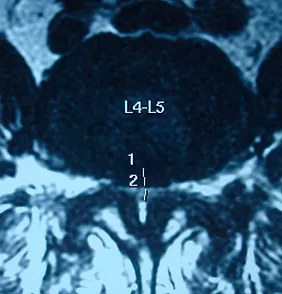

Классификация основанная на морфологическом состоянии дурального мешка и корешков спинного мозга на Т2-взвешанных изображениях МРТ поясничного отдела позвоночника в осевой плоскости. Классификация подразумевает деление стеноза на 4 класса, при этом 1-й класс делится на 4 подгруппы

Стеноз класса A: внутри дурального мешка ярко видна спинномозговая жидкость (СМЖ), но ее р аспределение является неоднородным.

A1: корешки расположены дорсально и занимают менее половины площади дурального мешка.

A2: корешки расположены дорсально, в форме подковы, касаясь твердой мозговой оболочки.

A3: корешки лежат сверху и занимают более половины площади дурального мешка.

A4: корешки расположены в центре и занимаются большую часть пространства дурального мешка.

​​

Стеноз класса B: корешки занимают все пространство дурального мешка. Некоторое количество спинномозговой жидкости присутствует, придавая структуре дурального мешка зернистость.

Стеноз класса C: нервные корешки не обнаруживаются, дуральный мешок демонстрирует однородный серый сигнал без видимого сигнала спинномозговой жидкости. Позади обнаруживается эпидуральный жир.

Стеноз класса D: в дополнении к тому, что невозможно обнаружить нервные корешки не визуализируется и эпидуральный жир позади.

Класс A определяется как отсутствие или незначительный стеноз, B как умеренный стеноз, C как тяжелый стеноз, и D как крайне тяжелый

стеноз.